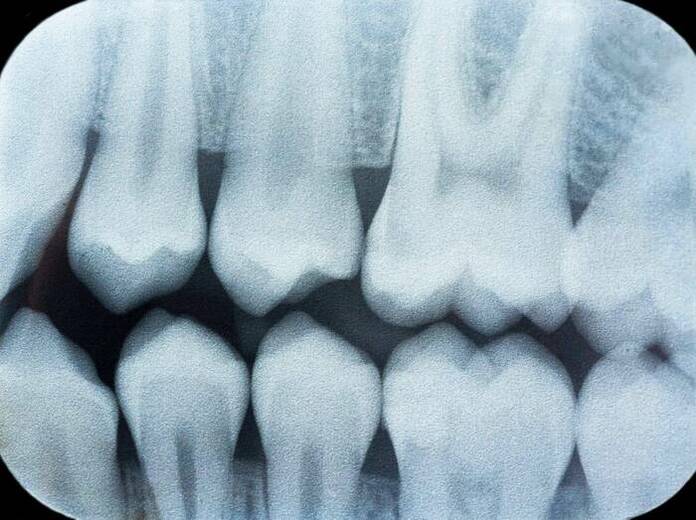

Con esta, se diagnostican distintas afecciones para diseñar los mejores tratamientos. Por ejemplo, logra identificar el grado de severidad en las caries, desde la estética hasta profundas infecciones en el nervio. En este último caso, el dentista programa una endodoncia en lugar del típico empaste.

Además, la radiografía panorámica distingue las enfermedades periodontales como la gingivitis y la periodontitis. En general, si el cliente presenta bolsas o abscesos, también se establece la profundidad y el tamaño, para drenar, efectuar canal radicular o la extracción del diente.